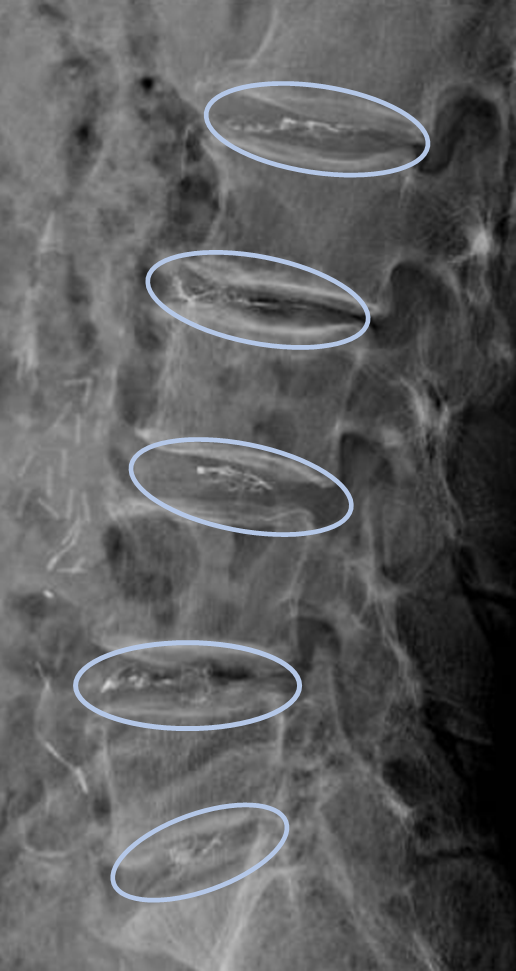

患者様と相談の元、L1/2,2/3,3/4,4/5,5/sにセルゲル法を施行

DiscoGelを入れた後の画像になります。